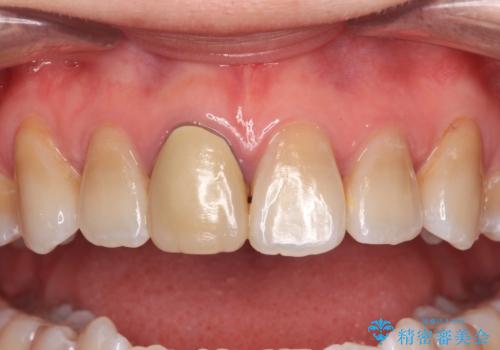

- 結婚式を前に、保険診療での前歯のクラウンが気になるとのことで来院された患者様です。

色合いだけでなく、歯肉の縁が黒くなっていることが分かります。

速やかに仮歯に交換し、オールセラミッククラウンにて補綴することとしました。